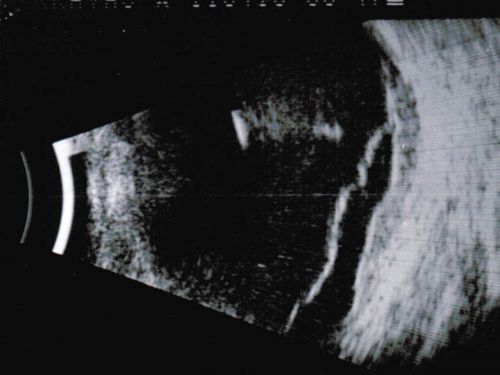

Choroidal Melanoma - Exudative Retinal Detachment 82 Year Old Man B Scan Ultrasound Longitudinal

82-year-old man who had 3 falls 2 weeks ago. After the falls he started checking his vision and noticed there was a veil over the left eye, which he had seen for about two weeks in the superior visual field.  OD 20/25,  OS 20/40

(patient was medically never well enough for brachytherapy and died 6 months later from heart disease)